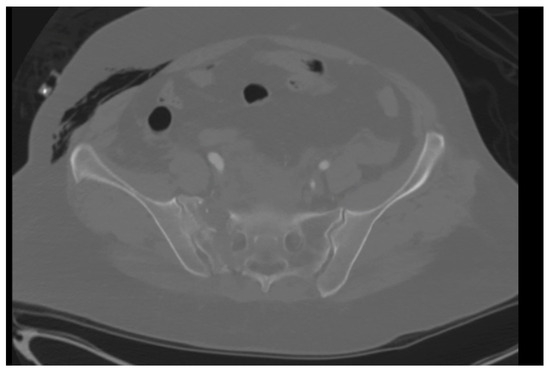

Figure 4.

Still image of coronal CT demonstrating lack of osseous union of vertical shear sacral fracture specifically surrounding trans-iliac trans-sacral screw in S1 corridor.